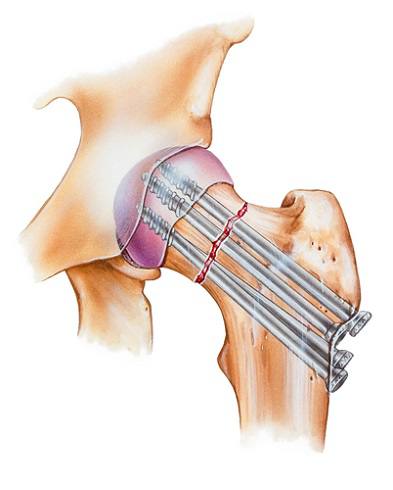

Yelka qopqog'i

Yelka bo'g'imi va o'mrov suyagi jarrohligida zamonaviy plitalar

Vintli fiksatsiya

Son bo'yni sinishlarini kanyullyar vintlar yordamida davolash